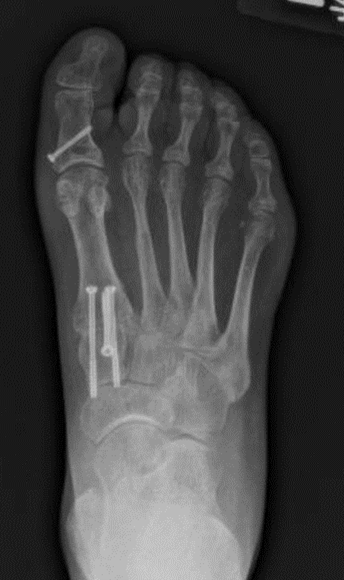

Lapidus bunionectomy

Figure 5: Lapidus bunionectomy with Akin osteotomy

A Lapidus bunionectomy involves a procedure called arthrodesis, which is the fusing of two bones. This procedure is used for severe bunions. During this procedure, the surgeon will make a cut in the medial midfoot to expose the first tarsometatarsal joint. The cartilage is removed from the joint and the 1st metatarsal and medial cuneiform bones are compressed and held in place with 3 screws. In addition, a distal soft-tissue procedure is performed. This requires an incision at the first webspace and the lateral soft tissues are released. You will be non-weight-bearing on the operative extremity for a minimum of 6 weeks to allow for healing and for the bones to fuse.